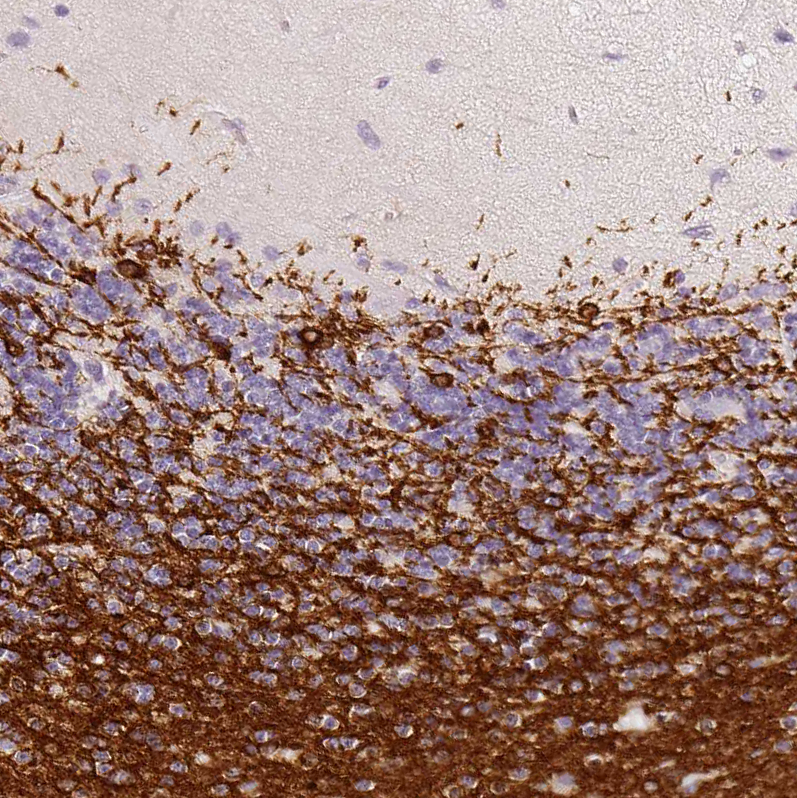

Immunohistochemistry analysis in human cerebral cortex and pancreas tissues using HPA023280 antibody. Corresponding CNP RNA-seq data are presented for the same tissues.